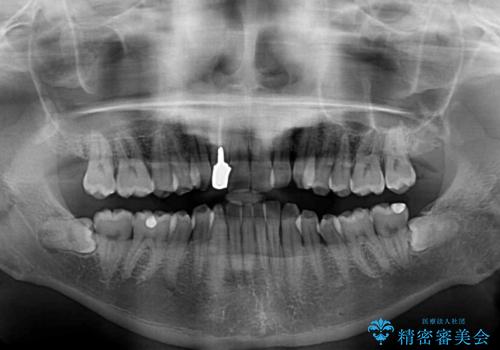

- 前歯のデコボコを気にして来院された患者様です。

目立たない装置で手軽に治したいとのことで、インビザラインにて矯正治療を行うこととしました。

前歯のクラウンは変色が著しいため、矯正治療後にオールセラミッククラウンにて補綴治療を行うこととしました。